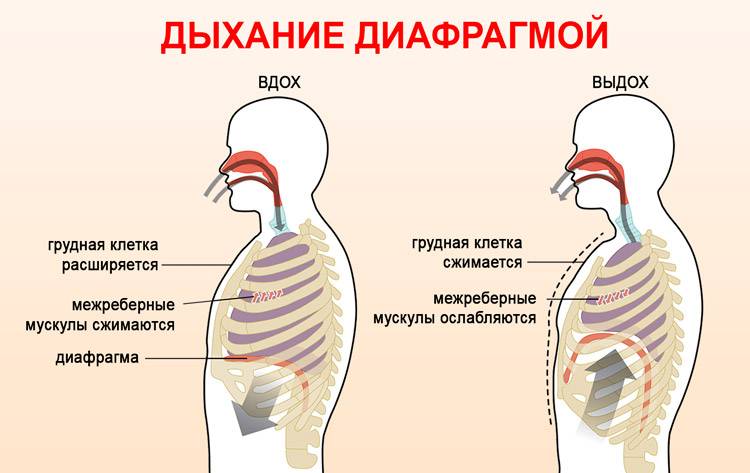

- Диафрагмальное (брюшное), когда в момент вдоха живот выступает вперёд, а на выдохе подтягивается по направлению к позвоночнику.

Главный орган в брюшном дыхании — диафрагма. Диафрагмальная мышца — это куполообразная перегородка, она отделяет грудную клетку от органов, расположенных ниже в брюшной полости. На вдохе диафрагмальная мышца идёт вниз и сжимается, заставляя брюшную стенку выдвигаться вперёд. В момент выдоха диафрагмальная мышца возвращается вверх и приобретает форму купола, выгоняя воздух из лёгких.

Важно! Диафрагмальное дыхание нужно выполнять только через нос. Дыхание ртом изменяет движение диафрагмы в направлении вперед-назад, что влечет за собой вред зажимов и помех для работы легких, в то время как глубокое носовое дыхание обеспечивает ее движение вверх-вниз и свободную работу дыхательной системы.. После освоения основ диафрагмального дыхания можно приступать непосредственно к самим упражнениям